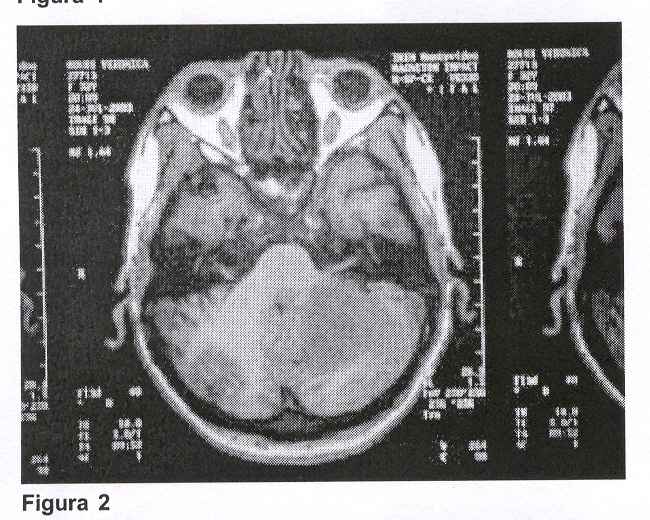

Con el planteo clínico de lesión ocupante de fosa posterior se solicitaron exámenes imagenológicos. La TAC, que fue realizada sin contraste, mostró una ligera atrofia cortical frontal bilateral sin otras anormalidades, por lo que se solicitó resonancia magnética de cráneo que mostró: "Proceso patológico en hemisferio cerebeloso izquierdo a nivel córtico-subcortical que se extiende a pedúnculos cerebelosos. Lesión de límites difusos con señal alta e inhomogénea en T2. Ligero efecto de masa con compresión del IV ventrículo. Aumento de su señal post contraste intravenoso persistiendo un área de señal baja a nivel central".